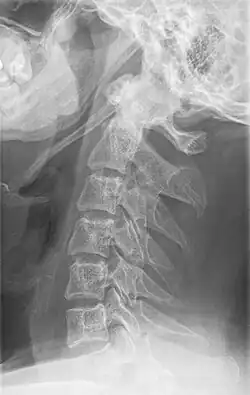

-

Radiograph, lateral view showing elongated stylohyoid process and stylohyoid ligament ossification -

Radiograph, lateral view showing joint-like formation in ossified stylohyoid ligament -